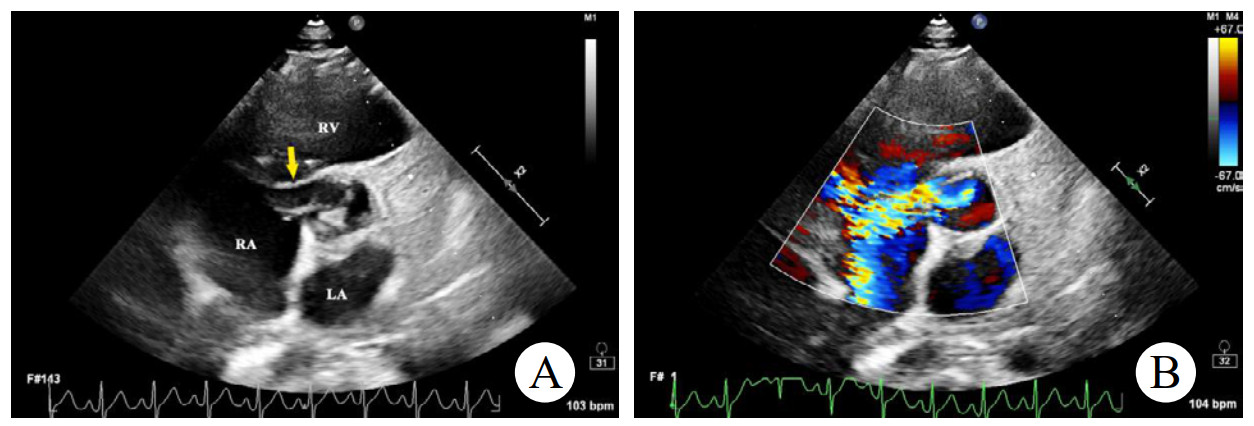

辅助检查如下。实验室检查:高敏C反应蛋白(hs-CRP)和红细胞沉降率(erythrocyte sedimentation rate, ESR)轻度升高。心电图:正常窦性心律,无ST段异常改变。胸部CT:双侧肺门中心对称分布的斑片状高密度影,部分实变,伴空气支气管征,病变边缘模糊。超声心动图:二维超声(2D)主动脉短轴切面显示右乏氏窦瘤破裂(ruptured of ASV, RASV),破入右心房形成“囊袋状”结构,长约1.7 cm,基底部破口内径约0.8 cm(图 1A)。彩色多普勒(color Doppler flow imaging, CDFI)显示全心动周期的左向右分流(图 1B)。连续多普勒(continuous doppler, CW)测得连续分流。室间隔内见4.0 cm×0.7 cm无回声区(图 2A),CDFI显示彩色血流信号随心动周期进出该无回声区(图 2B),考虑室间隔夹层瘤(dissecting aneurysm of the interventricular septum, DAIS)。实时双平面成像同步显示窦瘤破口与室间隔夹层相延续。应用Philips TrueVue三维(three-dimensional, 3D)超声心动图成像模式直观展示室间隔夹层瘤的立体结构(图 3)。

| 注:A为2D超声显示右乏氏窦瘤破裂(黄色箭头)突向右心房形成“囊袋状”结构;B为CDFI显示窦瘤破裂处自主动脉至右心房的左向右分流束 图 1 2D、CDFI显示主动脉短轴切面右乏氏窦瘤破裂情况 |